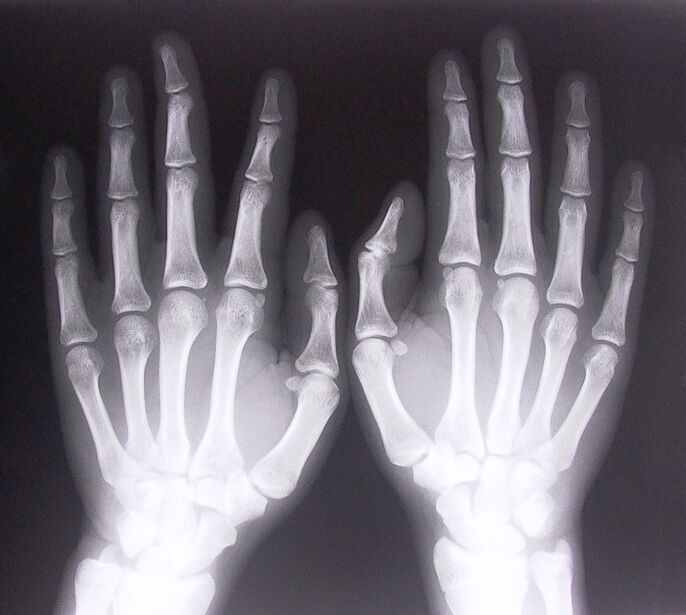

- Stenosing ligamentitis. Upang matukoy ang sanhi ng sakit, kinakailangang sumailalim sa x-ray. Ang mga sintomas ay tipikal: masakit na paggalaw ng kamay, pag-loop ng nakakuyom na palad. Gayundin, sa panahon ng extension, kadalasang maririnig ang mga pag-click.

Upang simulan ang paggamot sa magkasanib na sakit sa mga daliri, kailangan mong matukoy nang tama kung anong sakit ang sanhi nito. Upang matukoy kung anong uri ng sakit ang dumaranas ng isang tao na nakakaramdam ng sakit sa mga kasukasuan kapag baluktot ang kanilang mga braso, inirerekomenda ng mga doktor na sumailalim sa mga sumusunod na pamamaraan:

- Kumuha ng x-ray.

- Kumuha ng CT scan.

- Kumuha ng isang MRI.